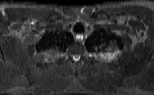

Visible Human male: Sectio transversalis 1323

CT

NMR

Pd T1 T2